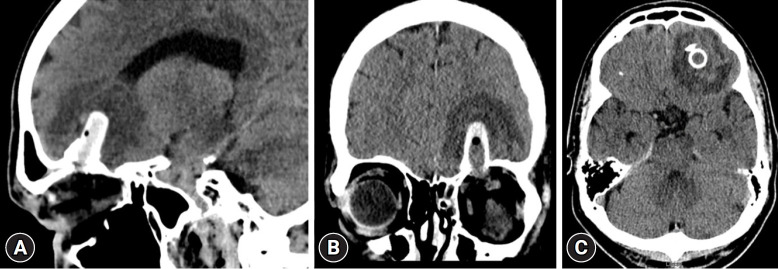

低速眼眶穿透伤可能导致颅内异物滞留,需要手术取出。我们描述了经眶内镜取出额叶内滞留的伞尖的手术,该异物继发于眶顶创伤。这项技术有助于彻底清除异物,而不会对周围组织造成额外损伤。患者术后恢复顺利。我们还讨论了经眶神经内窥镜手术在处理此类外伤时的实用性。

Low-velocity orbital penetrating injuries may result in an intracranial retained foreign body that requires surgical removal. We describe the endoscopic transorbital removal of a retained umbrella tip in the frontal lobe, which was secondary to trauma to the orbital roof. This technique facilitated the complete removal of the foreign body without causing additional damage to the surrounding tissue. The patient had a successful postoperative recovery. We also discuss the utility of the transorbital neuroendoscopic procedure in managing these traumatic injuries.